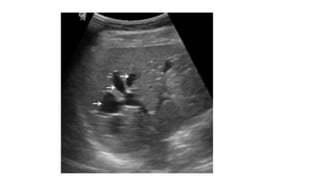

USG

• Ballooned/fusiform cyst beneath porta hepatis separate from GB

• *Communication with bile duct needs to be demonstrated*

• Abrupt change of caliber at junction of dilated segment to normal

ducts

• Intrahepatic bile duct dilatation secondary to stenosis.

Prenatal diagnosis

Ultrasound

Earliest diagnosis at 25 weeks

Ultrasound

USG • Ballooned/fusiform cystbeneath porta hepatis separate from GB • *Communication with bile duct needs to be demonstrated* • Abrupt change of caliber at junction of dilated segment to normal ducts • Intrahepatic bile duct dilatation secondary to stenosis.